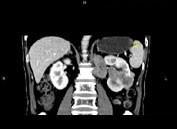

问题 男,65岁,左腰部隐痛不适2个月,CT平扫+增强如图所示,下列说法正确的是 ( )

选项 A、考虑为左肾癌伴肾门淋巴结转移 B、增强扫描可见左肾局部隆起左肾内的病灶强化方式相同 C、腹腔内未见积液,所示骨质亦未见破坏 D、平扫时可见左肾局部隆起,腹主动脉旁、肾门部有等密度的块影

答案 ABCD